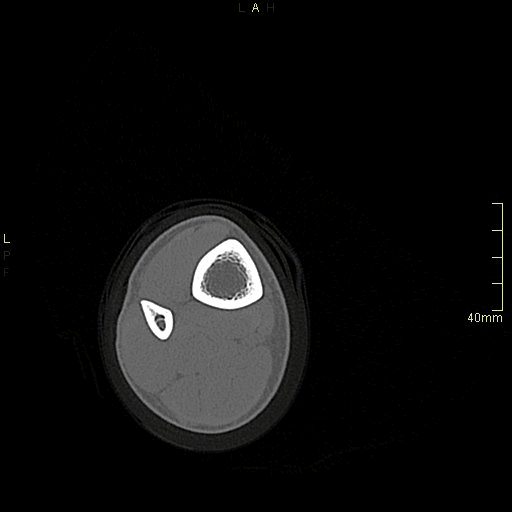

CT Ankle Contrast- Soft tissue window (axial)

CT Ankle Contrast- Bone window (axial)